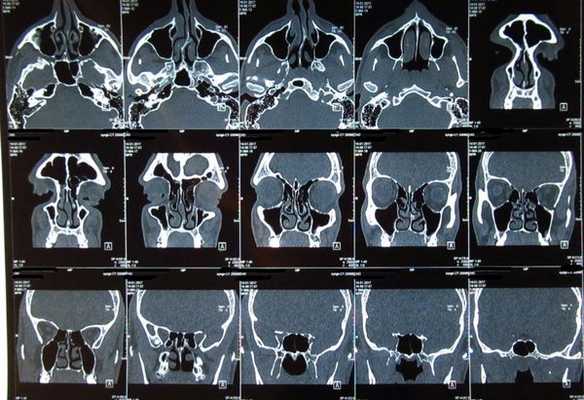

Компьютерная рентгеновская томография (КТ)

КТ является методом выбора при хронических синуситах, так как даёт возможность понять анатомические предпосылки к процессу. Основной диагностической плоскостью для шаговых КТ служит корональная. Срезы должны быть 2-3 мм толщиной и с высоким разрешением. Реформированные изображение имеют меньшее разрешение и, потому, нежелательны. Однако они могут стать вынужденной мерой при наличии артефактов от металлических зубных конструкций. Спиральная КТ позволяет уменьшить толщину срезов до 1 мм, что улучшает качество реформированных изображений. При использовании спиральной КТ нет необходимости во фронтальных укладках.

В костном окне хорошо виден остиомеатальный комплекс, а в мягкотканном - жидкость, полипы, распространение процесса за пределы синусов, в том числе на орбиту, подвисочную ямку и мозг.

Наиболее типичной находкой при острых синуситах является полипозное утолщение слизистой. В пазухе может быть выявлена жидкость, причем её заполнение может быть полным или частичным. При хронических синуситах часто вовлекаются клетки решетчатой кости. Помимо утолщенной слизистой видны полипы и ретенционные кисты. Ретенционные кисты (мукоцеле) чаще всего наблюдаются в лобных и верхнечелюстных пазухах.

Главным недостатком КТ является сложность в дифференцировке опухоли, локализующейся в синусе, от застойной жидкости.

Правосторонний этмоидит (стрелка). КТ. Фронтальная плоскость.

Киста (мукоцеле) лобной пазухи. КТ. Фронтальная плоскость.